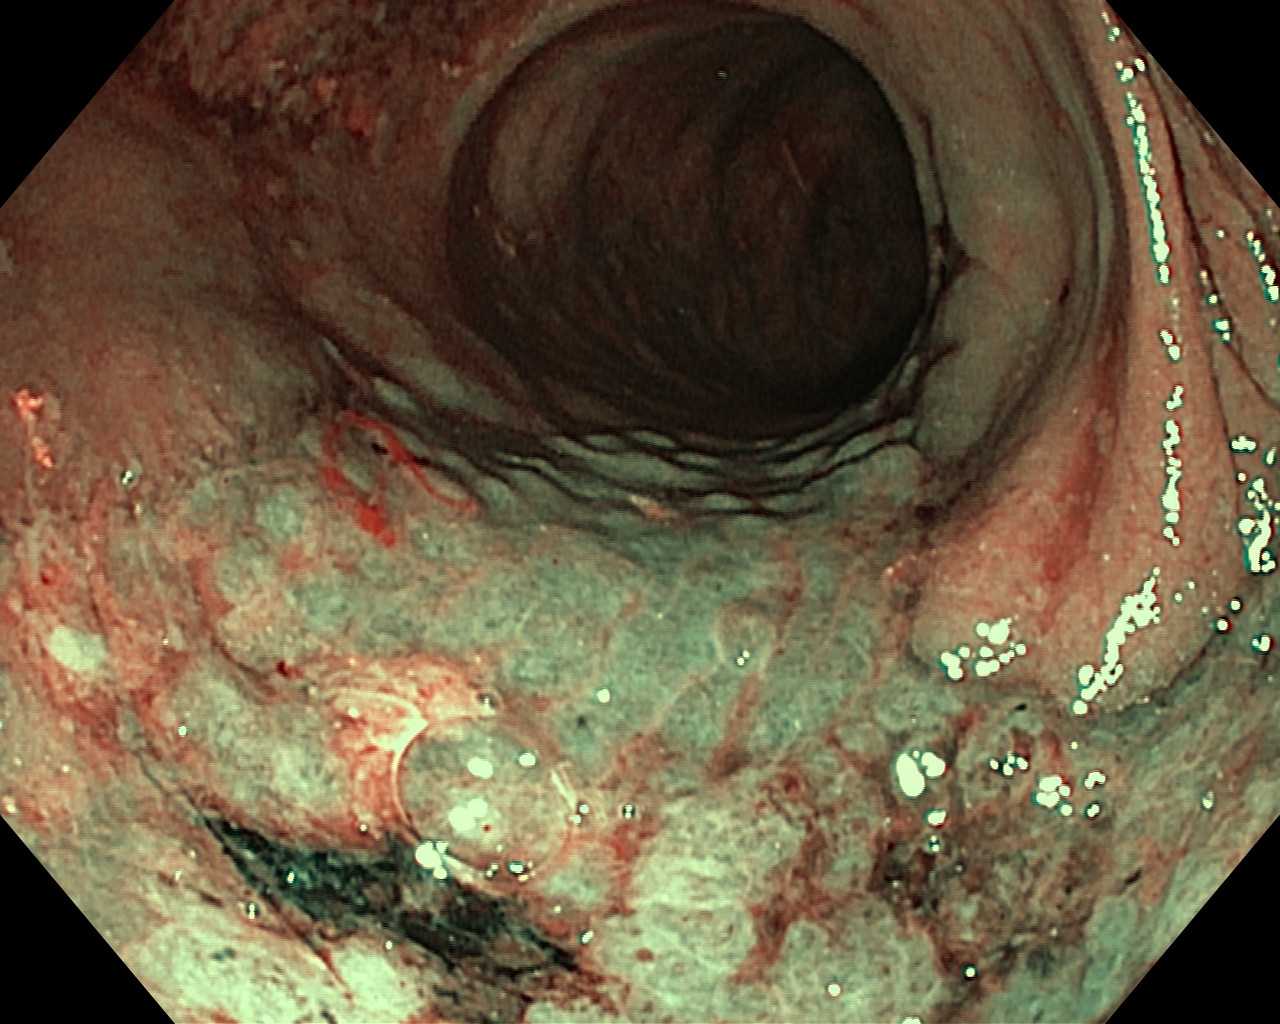

Nowotwory przewodu pokarmowego